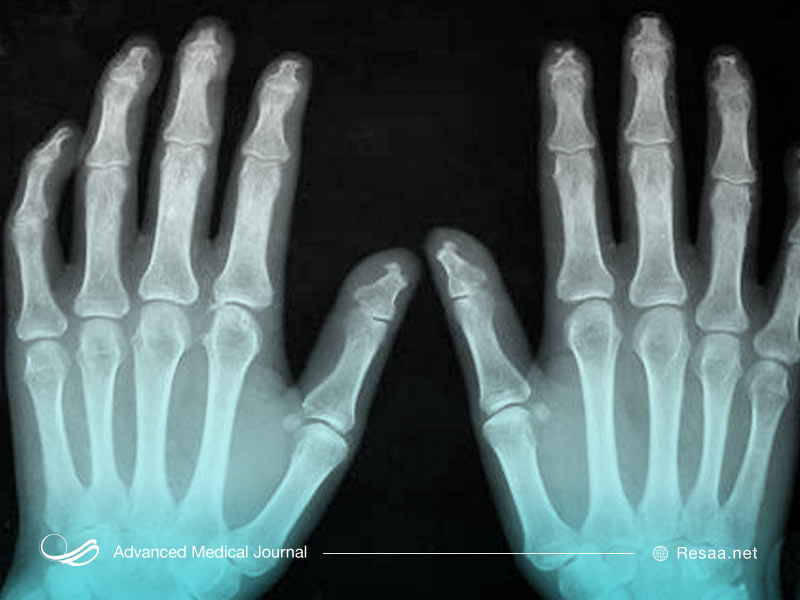

- Sاسکلرو داکتیلی )سفت شدن پوست روی انگشتان(

بیماران مبتلا به اسکلرودرمی محدود، مشکلات کلیوی را تجربه نمیکنند. ضخیم شدن پوست به انگشتان، دستها و بازوها و همچنین گاهی اوقات به پاها محدود میشود. درگیری گوارشی بیشتر به مری محدود میشود.

پس از بحث در مورد سابقه پزشکی خانوادگی، پزشک معاینه کامل بدنی را انجام میدهد. با این کار، وی به دنبال هر یک از علائم ذکر شده در بالا، به ویژه ضخیم شدن یا سفت شدن پوست اطراف انگشتان دست و پا یا تغییر رنگ پوست خواهد بود. در صورت مشکوک بودن به اسکلرودرمی، آزمایشاتی برای تأیید تشخیص و همچنین تعیین شدت بیماری انجام میشود.